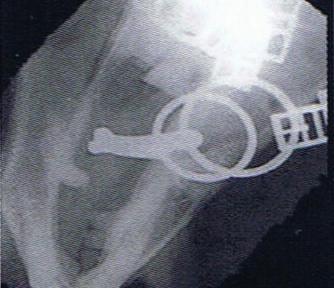

Radiographic proof in clinical results

BONE Gold nutritional bone joint and collagen supplement was formulated to provide some of the essential amino acid requirements of collagen type I, II and III (found in bone and connective tissue) in addition to supporting the nitric oxide pathway which has been found to assist in the formation of bone callus postinjury.

Veterinary surgeons have recommended that Bone Gold may assist with sore shins, tendon injuries, ligament injuries, osteoarthritis and post-surgery in horses and polyarthritis, geriatric osteoarthritis, and post-surgery in dogs.

Here is a veterinary radiographic report on a horse with a fracture evident on the medial toe and after treatment and feeding Bone Gold during this period. More information on these products can be found at www.vetgold.com.au

26.08.21: Right Front: Large P3 solar margin fracture evident on medial toe 32.6mm x 4.1mm with approximately 1.4mm separation from parent bone as below left image.

21.10.21: Right Front: Fine residual 4.2mm fracture still evident, approximately 90% resolution

17.11.21: Right Front: Fracture fully resolved

Radiographic results as of the 17th Nov '21 show total resolution of the original fracture.

Solar margin Type IV fractures of this magnitude have well-documented internationally published healing rates of 7 - 12 months. Full resolution of these fractures is rare as most often the fracture fragments are resorbed. Full resolution in a 3 month period was not anticipated.

The horse was on Bone Gold 3 x scoops fed once per day for this period.